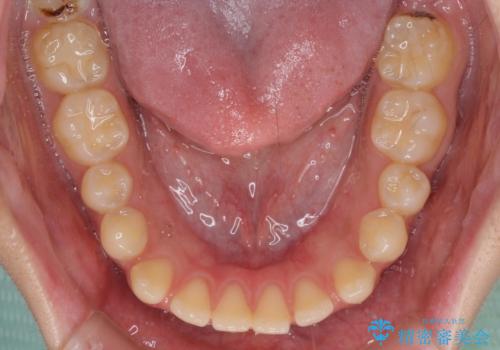

【モニター】隙間だらけの前歯を治したい インビザラインによる矯正治療

- 上下前歯の隙間と咬み合わない前歯を気にして来院された患者様です。

開咬の治療は、前歯を閉じるように動かすとともに、上下臼歯を圧下(骨内にめり込ませる)させることで進めて行きます。

インビザラインは臼歯の圧下を効果的に行えるため、インビザラインを用いて矯正治療を行うこととしました。

開咬とすきっ歯は、舌の突出癖改善が必須となるため、トレーニングを徹底的に行うよう指示しました。